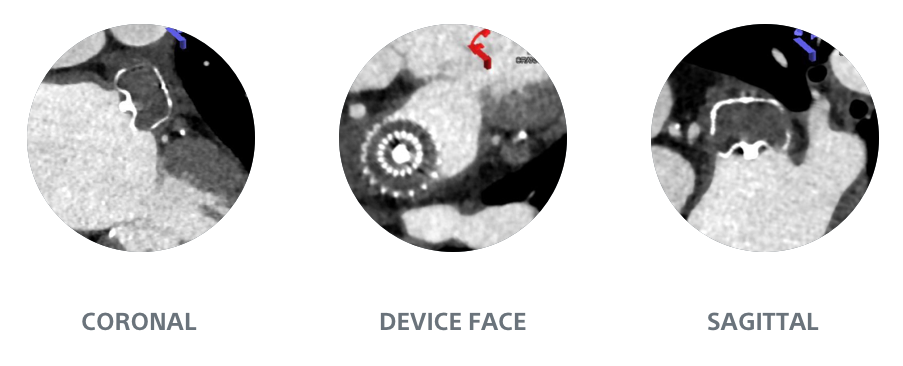

Simplified Assessment

WATCHMAN FLX1

Full Visibility

AMPLATZER AMULET1

Hidden Leaks